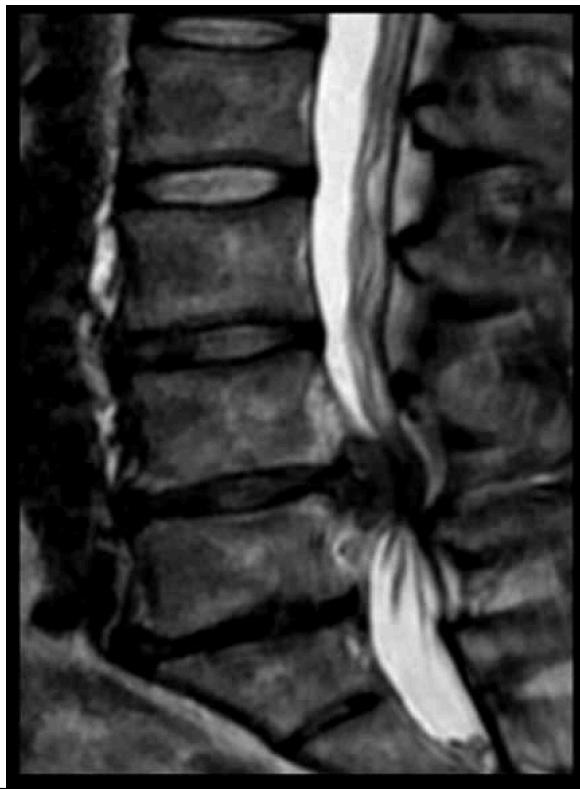

Cauda Equina Syndrome Z

- Etiology: Severe compression of nerve roots in the thecal sac of lumbar spine, most commonly due to acute lumbar disc herniation

- Critical: Early diagnosis is essential

Clinical Features:

- Back pain (most common)

- Unilateral or bilateral leg pain (2nd most common)

- Saddle anesthesia (highly specific)

- Bladder dysfunction: Urinary retention → overflow incontinence

- Unilateral or bilateral sensory changes in legs

- Unilateral or bilateral motor weakness in legs

Diagnosis:

- Urgent MRI to confirm cause

Treatment:

- Prompt surgical decompression

- Should be performed within 24 hours, absolutely within 48 hours